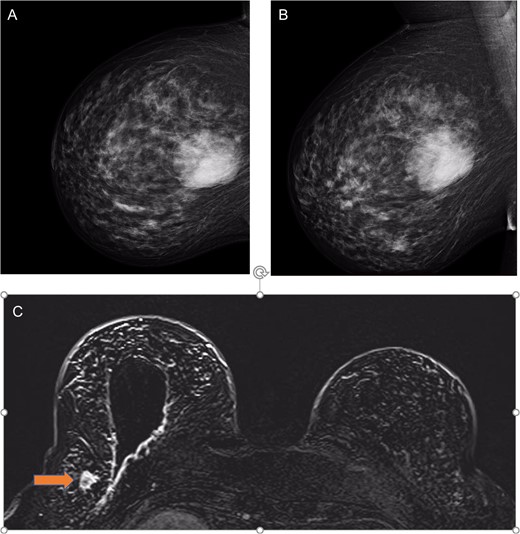

A 48-year-old asymptomatic woman presented to breast screen, where mammogram identified a 65 mm right breast lesion at 10 o'clock region. She was overweight and had sleep apnoea, diabetes mellitus, hypertension, dyslipidemia and subclinical hypothyroidism. She had a family history of breast cancer in two second degree relatives (paternal grandmother diagnosed at ~60 years and maternal aunt diagnosed 58 years). Mammogram reported a Tabar grade 3b relatively well circumscribed lesion in right breast measuring 65 mm located 10 mm from nipple at 10 o'clock (Fig. 1A and B) and no other lesions. There was no associated microcalcification but some non-specific irregularity laterally and around the mass. At ultrasound, the main lesion appeared avascular and no other breast lesions were identified in both breasts. Histopathology of the core biopsy showed an atypical fibroepithelial lesion with features suspicious of a PT.

(a) Right mammogram cranial–caudal and (b) medial lateral oblique views showing the 65 mm phyllodes tumour; and (c) MRI T1 views with post-surgical wide local excision cavity and synchronous lobular carcinoma (labelled by orange arrow).

Histological examination showed lobular carcinoma in situ within in the re-excision margin (Fig. 2B) with the right axilla sentinel lymph node identifying metastatic lobular carcinoma. On re-discussion at the multi-disciplinary team meeting, a mastectomy and axillary clearance was recommended. A screening breast MRI was performed to identify the mammographically occult lobular breast cancer and exclude a contralateral carcinoma. It showed post-operative changes and a 20 mm focal enhancement in the lateral right breast, 2 cm lateral to the surgical cavity, which was suspicious for a breast carcinoma (Fig. 1C).